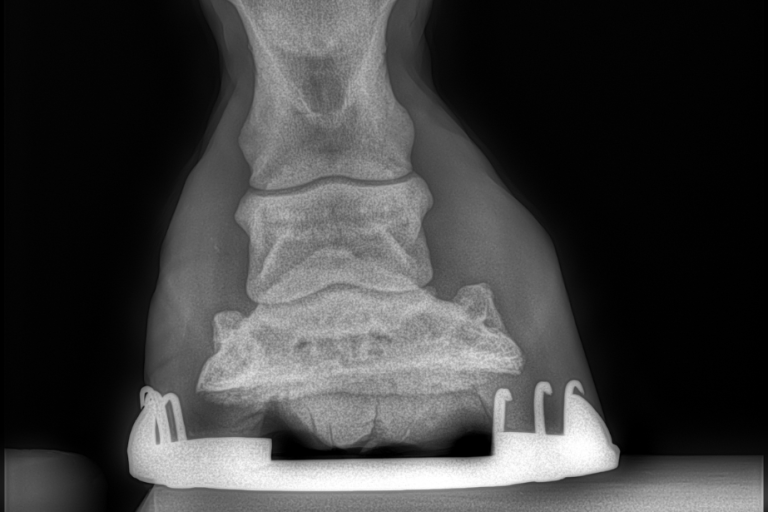

Dorntherapie

Die Dorntherapie ist eine manuelle, sanfte Wirbel- und Gelenktherapie, bei der mit Eigenbewegung des Hundes beziehungsweise des Pferdes das Skelett wieder in die Statik gebracht wird und Blockaden gelöst werden.